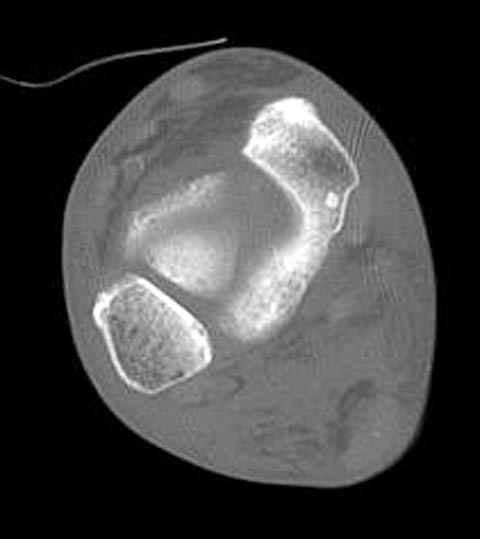

В декабре у меня был пациент с политравмой и аналогичным повреждением тарана с подвывихом в таранно- ладьевидном суставе, единственное отличие - отломок головки тарана был меньше по размеру и фрагментирован, поэтому его фиксация была невозможна.

Для доступа к задне-медиальному суставному фрагменту я выполнил косую остеотомию внутренней лодыжки у её основания -получается хороший доступ к голеностопу, адекватный обзор и возможность восстановить суставную поверхность. фрагмент фиксировал двумя 3,5 мм спонгиозными винтами с неполной резьбой, *утопив* головки винтов в кость. Аналогичная фиксация и двумя тягловыми винтами и внутренней лодыжки. \в качестве альтернативы для

фиксации фрагмента тарана можно было бы использовать и герберт винты, но по организационным причинам :-(( набора не оказалось под рукой).

Вывих в таранно-ладьевидном суставе удалось вправить с помощью Howard retractor, используя его в качестве рычага.Сегодня искал в рентген архиве